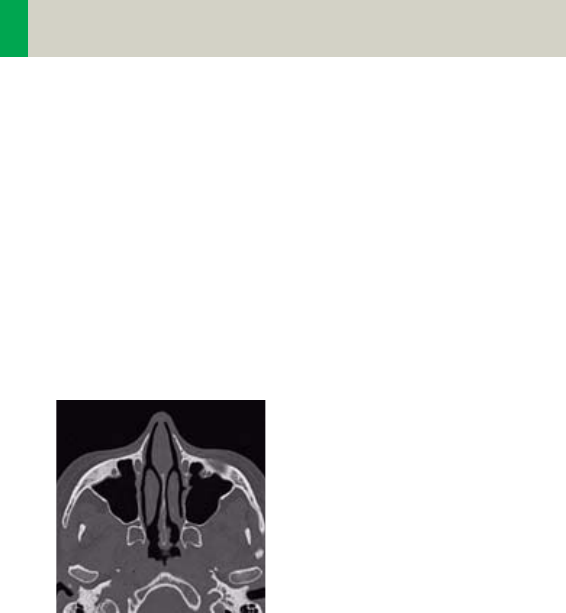

Positioning

In order to optimize image quality versus radiation

dose, scans in body regions “Head” and “AngioHead”

are provided within a maximum scan field of 300 mm

with respect to the iso-center. No recon job with a field

of view exceeding those limits will be possible. There-

fore, patient positioning has to be performed accu-

rately to ensure a centered location of the skull.

correct positioning wrong positioning

of the head of the head

For trauma examinations of the head we provide two

protocols, to be found in the specials folder:

– HeadTrauma

– HeadTraumaSeq.

The scan protocols enable you to utilize the full 50 cm

FoV, resulting in easier patient positioning for trauma

examinations and to ensure the highest performance,

the dedicated PFO head filter is not used.